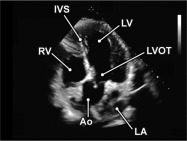

| 2.2. Mặt cắt trục dài cạnh ức khu trú vào thất trái

|

||||||||

|

|

Cửa sổ siêu âm cạnh ức

Mặt cắt trục dài cạnh ức Đầu dò đặt tại bờ trái xương ức với marker hướng lên vai phải của bệnh nhân. Chùm siêu âm đặt vuông góc với thất trái. |

Nhĩ trái (LA)

Van hai lá (MV) Thất trái (LV) Đường ra thất trái (LVOT) Van động mạch chủ (AV) Vách liên thất (IVS) Thất phải (RV) |

|||||